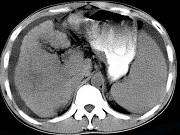

问题 男,35岁,有乙肝病史多年,AFP阳性,影像检查如图,最可能的诊断是()

选项 A.肝硬化腹水 B.肝血管 C.肝脓肿 D.肝癌、硬化腹水 E.肝硬化,结节性增生

答案 D